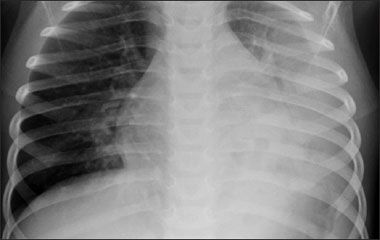

Figure 1 – In this radiograph, obtained during the patient's first episode of pneumonia, cystic lucencies visualized within the left lower lobe are representative of a necrotizing presentation.

History. The patient was born to a gravida 1 para 1 mother via normal vaginal delivery after an uncomplicated pregnancy. She was first seen by her current pediatrician for a well-child visit at age 15 months. At that time, the mother noted that her daughter had had 4 episodes of otitis media in the preceding 3 months. When she was 18 months old, a necrotizing pneumococcal pneumonia developed (Figure 1), for which she was hospitalized. Although the culprit organism was not resistant, the child's condition did not respond to initial antibiotic therapy. During the 10-day hospitalization, she required intravenous antibiotics and a pleural chest tube. Following hospital discharge, she received therapy with oral amoxicillin for 4 weeks. The month following discontinuation of the amoxicillin-while she was still healthy-the patient received the pneumococcal vaccine. Nine months later, pneumonia was diagnosed again; this time, treatment with intramuscular ceftriaxone was successful.